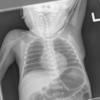

Normal neonate

Date: 02/07/2010

Views: 5816